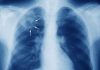

Nampula (IKWELI) – Os serviços de urgência do Hospital Central de Nampula (HCN), maior unidade sanitária da região norte do país, tem estado a receber pacientes que contraíram ferimentos graves e ligeiros, durante a manifestação, convocada pelo candidato a presidência suportado pelo partido PODEMOS, Venâncio Mondlane.

De acordo uma fonte oficial do HCN, os profissionais de saúde estão a fazer o possível para registar os casos e dar o devido tratamento aos feridos.

A fonte deu a conhecer que o HCN poderá pronunciar-se oportunamente para falar sobre o estado dos pacientes que neste momento estão a receber tratamentos médicos. (Virgínia Emília)